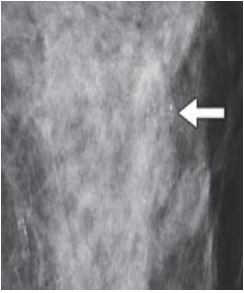

The distribution of calcifications is as equally important as the morphology of calcifications.

B. Regional - where >2cm (lower limit) of breast tissue is occupied. Malignancy is less likely since they do not have a ductal distribution.